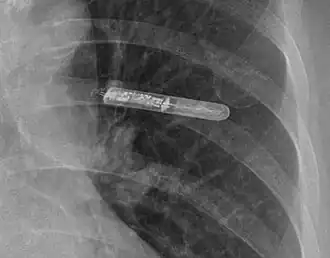

An implantable loop recorder (ILR), also known as an insertable cardiac monitor (ICM), is a small device that is implanted under the skin of the chest for cardiac monitoring, to record the heart's electrical activity for an extended period.[1]

The ILR is implanted by an electrophysiologist under local anesthesia. A small incision (about 3–4 cm or 1.5 inches) is made just lateral to the sternum below the nipple line, usually on the patient's left side.[8] A pocket is created under the skin, and the ILR is placed in the pocket. Patients can go home the day of the procedure with few restrictions on activities.[4] Bruising and discomfort in the implant area may persist for several weeks.